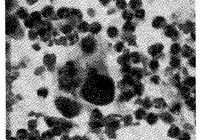

2.1 Ⅰ型细胞学特征:细胞多分散,胞体大,园形,细胞膜清楚,胞浆丰富,细胞核大较园,核染色质增多,分布不匀,细胞异型性小。(图1、图2)。

图1 原位癌

图2 早期浸润性鳞癌